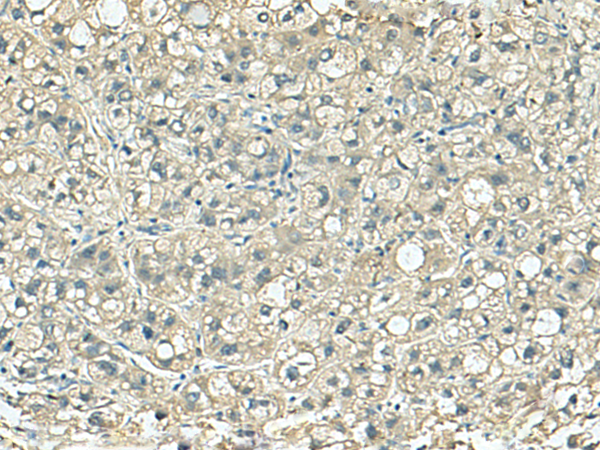

IHC positive control:

Human liver cancer

IHC Recommend dilution:

150-300